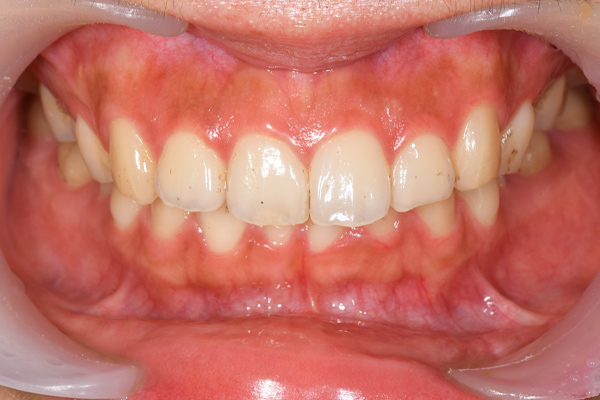

オフィスホワイトニング症例

治療前

治療後

主訴 歯を白くしたい

治療

内容

オフィスホワイトニング5回

方針

オフィスホワイトニング

期間

1ヶ月

費用 合計16,500円

オフィスホワイトニング5回 16,500円

(2022年7月現在)

リスク

副作用

知覚過敏が起こる・ホワイトスポット出現の可能性があります。 詰め物・被せ物は白くなりません。

ホワイトニングの効果は永久的ではなく徐々に色戻りします。

担当

者所見

短期間で白さが得られたと患者さまも満足されていました。白さのキープの為にホームホワイトニングも行う予定です。